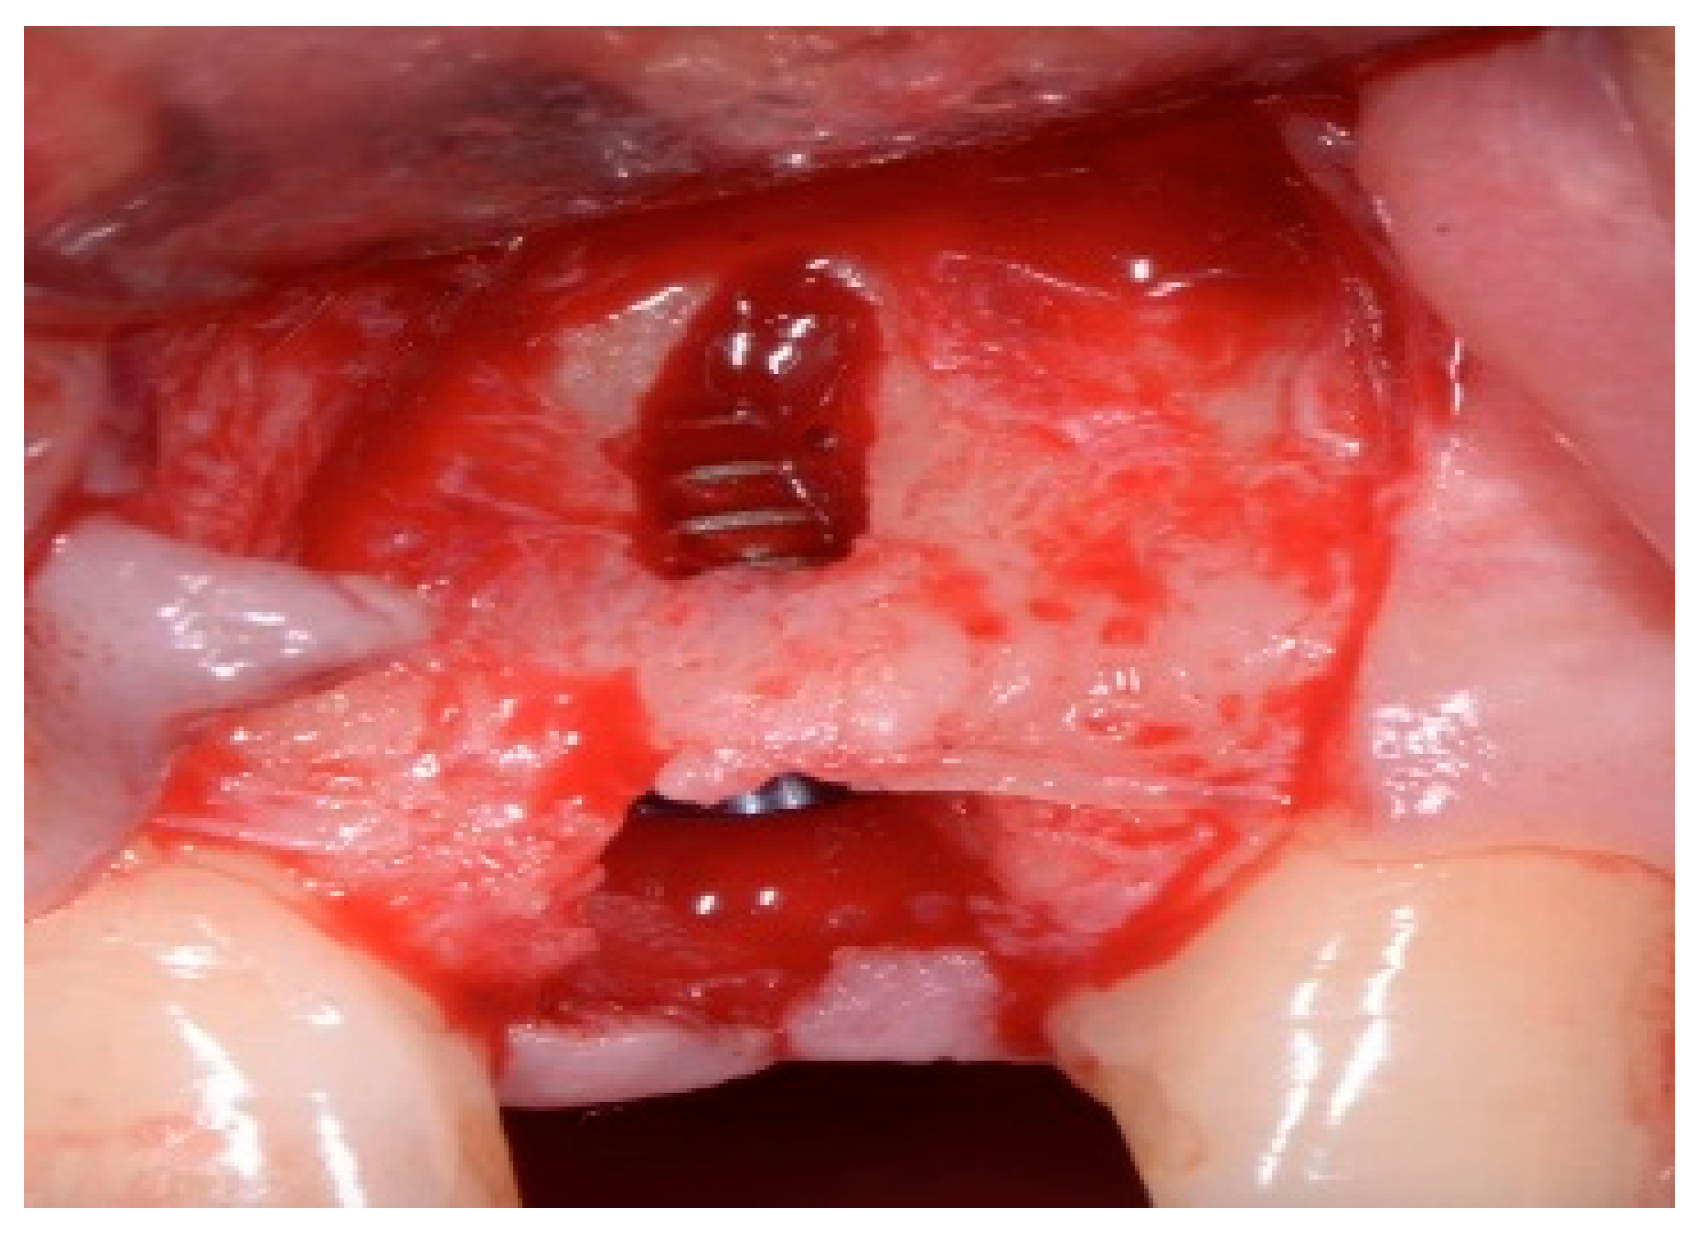

One hour before the surgical procedure, the patient received a prophylactic dose of 1 g of amoxicillin. Following local anesthesia, surgical access was obtained by raising a full-thickness aesthetic flap extending to the distal line angles of the lateral incisors. The full-thickness flap was extended 3–5 mm beyond the apical margin of the defect. The two central incisor roots were extracted, and the sockets were curetted with surgical curettes to remove all the granulation tissue (Figure 2). The sockets were assessed for the presence of a dehiscence and or fenestration. Two implants (Adin Dental Implants, Englewood, NJ, 07632, USA) were placed according to the manufacturer’s instructions (Figure 3).

Figure 2.

Clinical view immediately after extraction.